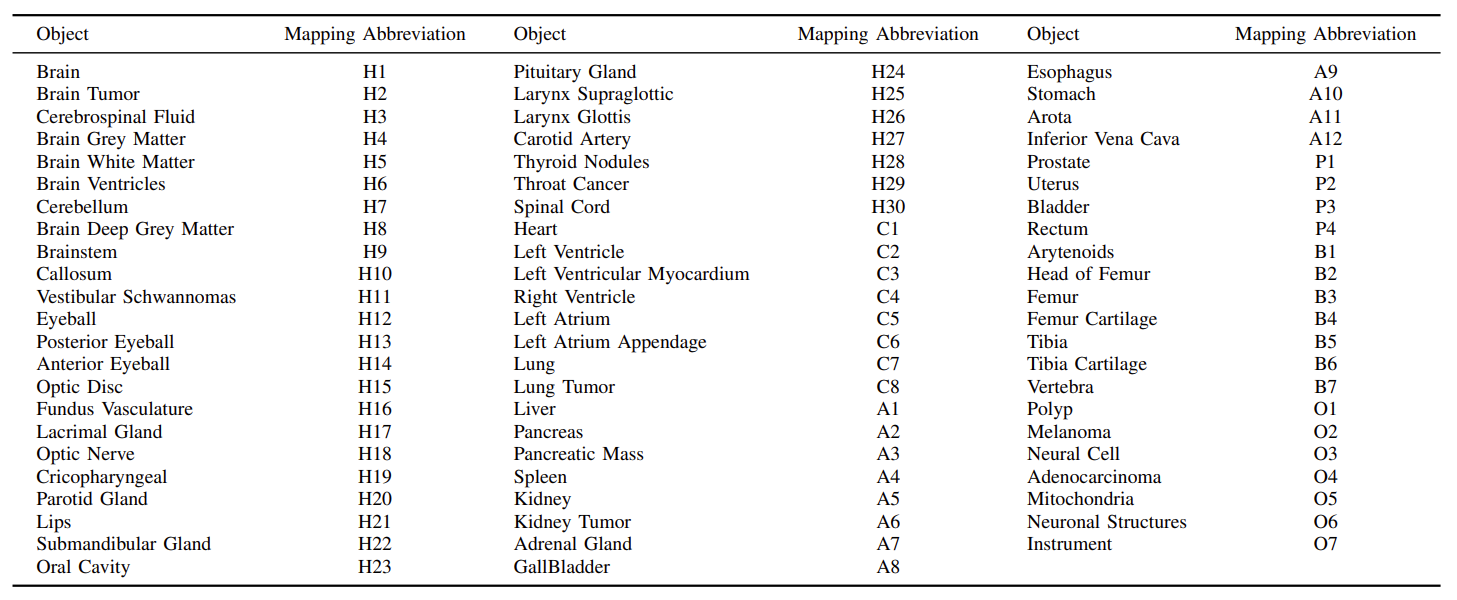

为了全面评估分析SAM在医学影像分割上的表现,团队收集并标准化了52个公共数据集,最终整理构建了一个包含16种影像模态和68种生物医学领域分割目标(表1)的大型医学影像分割数据集COSMOS 553K,数据集的展示见图1,统计信息见图2:

表1 COSMOS 553K包含的分割目标。H:头颈部;C:胸部;A:腹部;P:盆部;B:骨头;O:其它。

图1 COSMOS 553K涵盖了大多数医学影像模态和生物医学领域分割目标。例如,脑肿瘤、眼底血管、甲状腺结节、脊柱、肺、心脏、腹部器官或肿瘤、细胞、息肉和手术仪器等。人体图像来自Freepik,作者为brgfx(网址)